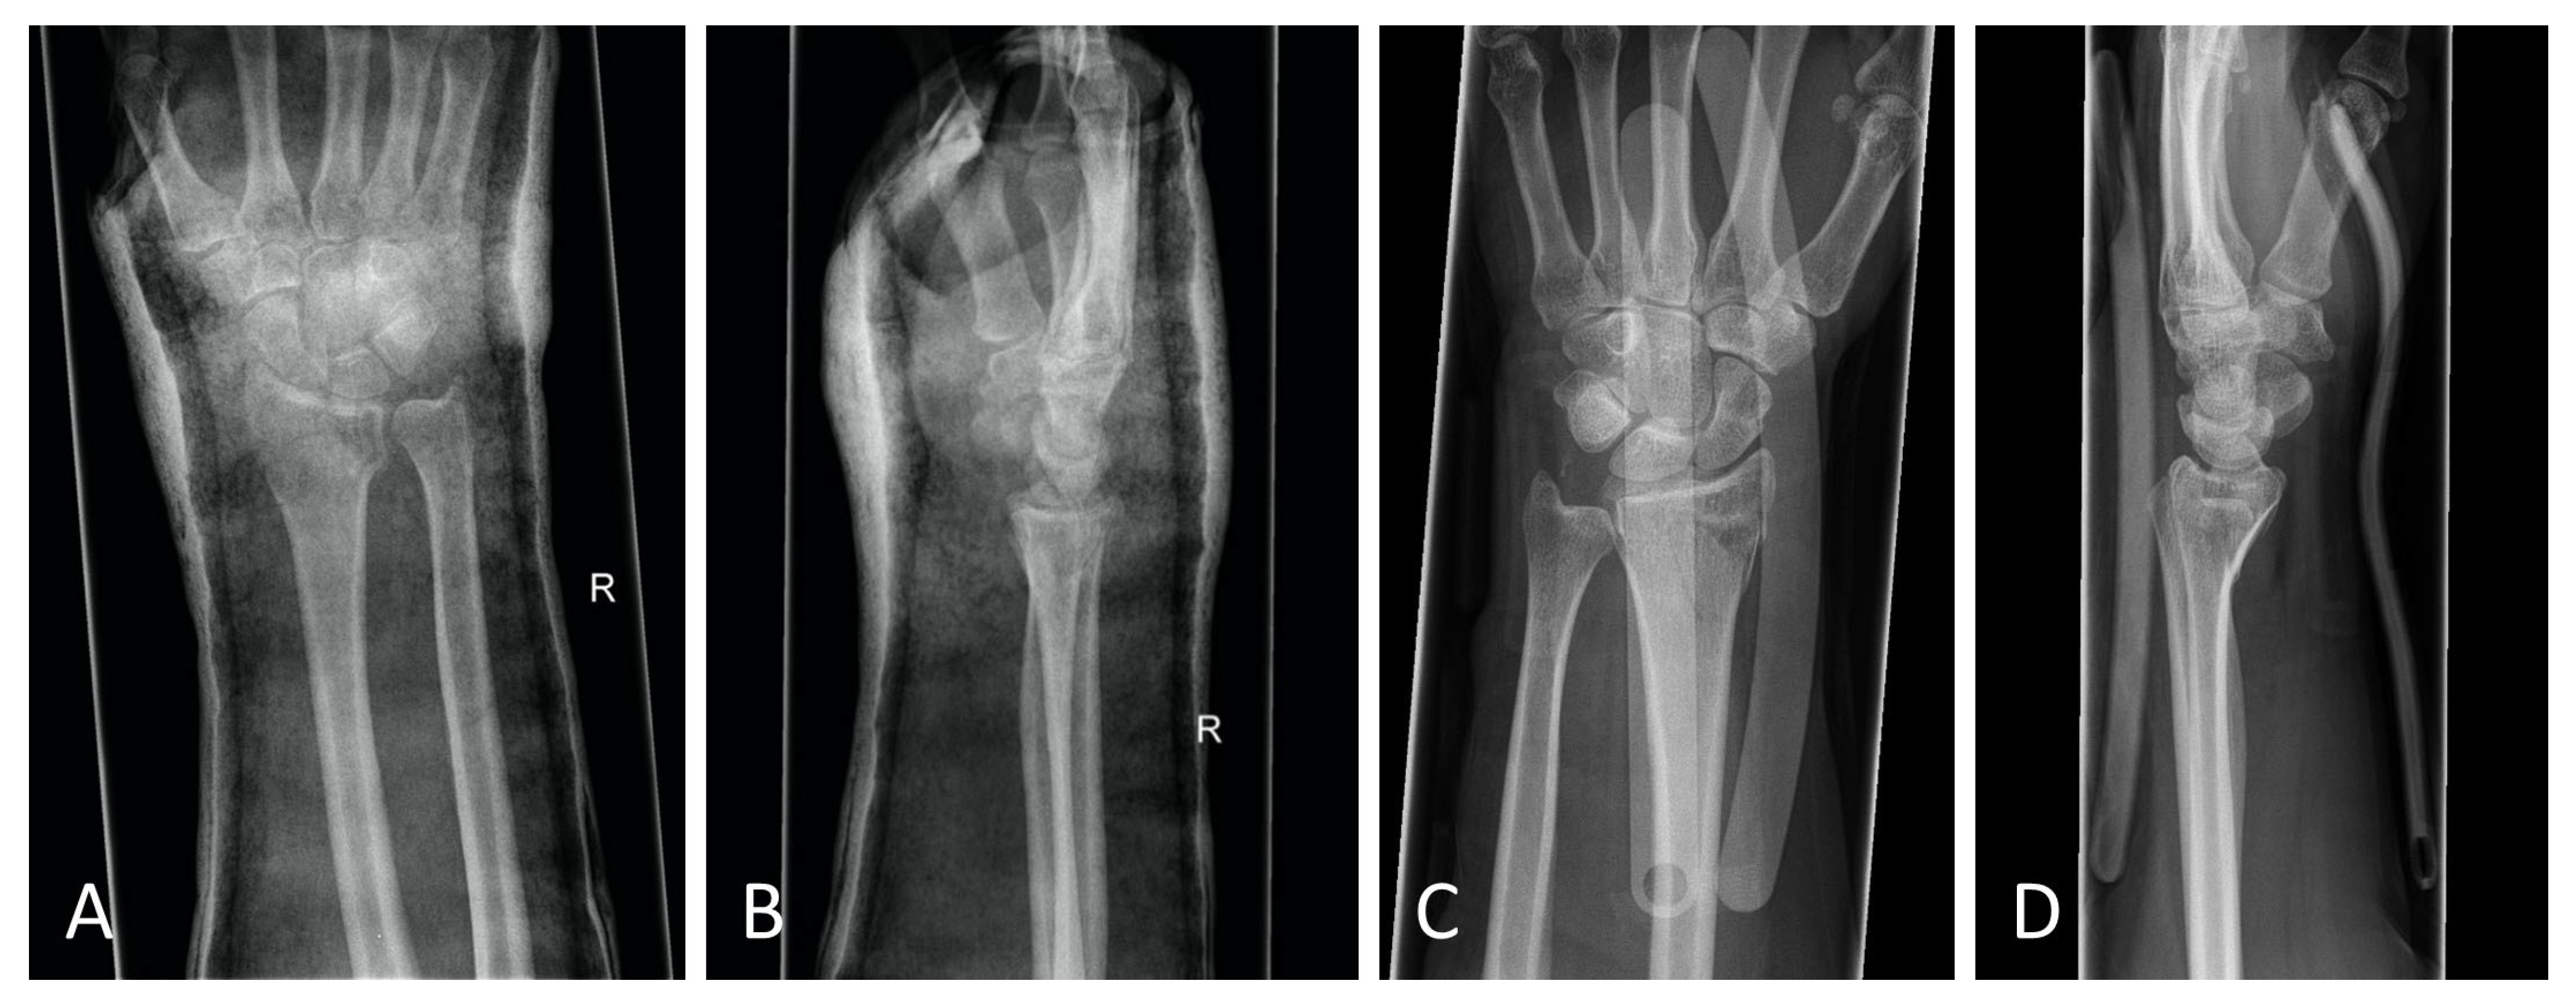

Figure 6.

(A) Posteroanterior radiograph with cast. (B) Mediolateral radiograph with cast. (C) Posteroanterior radiograph with orthosis. (D) Mediolateral radiograph with orthosis. All radiographs were taken after reduction before surgery.

The standard treatment approach in our Level I trauma center was not altered by the study protocol, except from the placement of the orthosis. In our approach, we were able to adjust the orthosis used immediately during finger-trap traction and show that there was no increase in secondary dislocations on the radiographic and CT control imaging and, moreover, that diagnostic procedures were in no way restricted when the orthosis was in place. The quality of detail was not limited in any way in the lateral projection, very less in the posteroanterior view (Figure 6A–D). Additionally, the use of the orthosis did not affect the CT scan. As shown in Figure 7, there are no metal artifacts induced by the aluminum splints. Hence, modern orthoses enable comprehensive radiographic diagnostics.